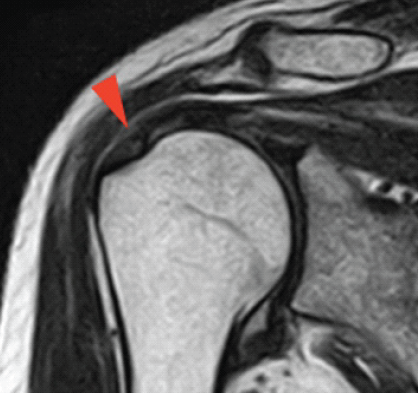

Postoperatively, passive range-of-motion exercises were initiated at 2 weeks, followed by active exercises beginning at three weeks. At 6 weeks, the patient developed recurrent shoulder pain and mechanical catching. Despite continued rehabilitation, symptoms gradually worsened. At 6 months postoperatively, MRI demonstrated a hypointense structure within the subacromial bursa (Fig. 3). Suspecting this to be the cause of symptoms, repeat arthroscopy was performed.

Figure 3: Post-operative coronal T2-weighted Magnetic resonance imaging (MRI) showing loose body within subacromial bursa. Coronal T2-weighted MRI of the right shoulder performed 6 months postoperatively, demonstrating a hypointense structure (arrowhead) within the subacromial bursa, consistent with a loose body formation. The previously torn rotator cuff appears to have been repaired.